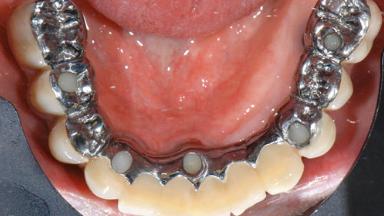

Repeated Acrylic Fractures on a Mandibular Fixed Full-arch Implant-supported Metal/Acrylic Prosthesis

A 77-year-old male patient was referred for the management of frequent and repeated acrylic fracture of his existing mandibular fixed full-arch implant-supported metal/acrylic prosthesis. He also complained about softtissue soreness and the lack of retention and stability of his maxillary removable partial metal/acrylic prosthesis. Both prostheses had been delivered two years previously as part of his full-mouth rehabilitation (caries, tooth wear, tooth fracture). His medical history revealed high blood pressure, controlled with the use of antihypertensive medication.

Defining Characteristics Fully edentulous lower jaw to be rehabilitated with an implant-borne fixed dental prosthesis

Retention Screw-retained, with 4 or more splinted implants Screw-retained, with 4 or more splinted implants